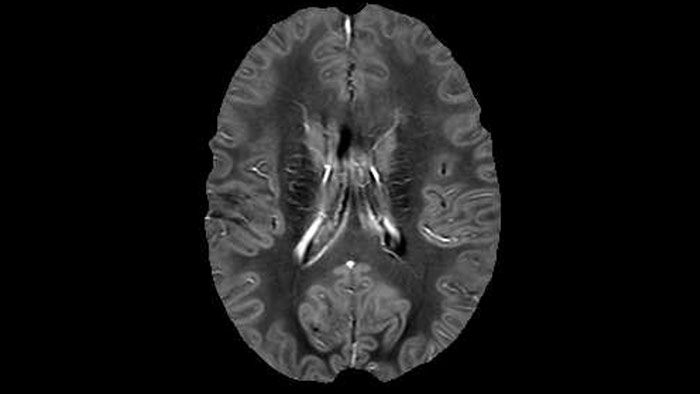

Juxtacortical MS lesion elition

Sagittal 3D FLAIR with 0.3 mm3 voxel volume acquired in 5:12 min. using Compressed SENSE showing a (juxta)cortical MS lesion.

QSM elition Kames algorithm

QSM based on a Compressed SENSE multi-echo SWI.

He says the accelerated scanning is achieved via the use of Compressed SENSE and MultiBand SENSE. “We can use Compressed SENSE acceleration factors of about 10 on a 3D FLAIR for instance, which is quite remarkable compared with what we saw with the Achieva. With 3D FLAIR, we can push the spatial resolution to 0.3 cubic mm and it works. Previously, our 3D FLAIR scans lasted about 8 minutes, but now with Elition they are five minutes. The SNR is also visibly better. Our SWI and QSM scans look fantastic. Also, since a lot of neuroimaging is EPI based, using the MultiBand SENSE technique can increase temporal resolution and make it possible to run complicated DTI scans relatively quickly.”